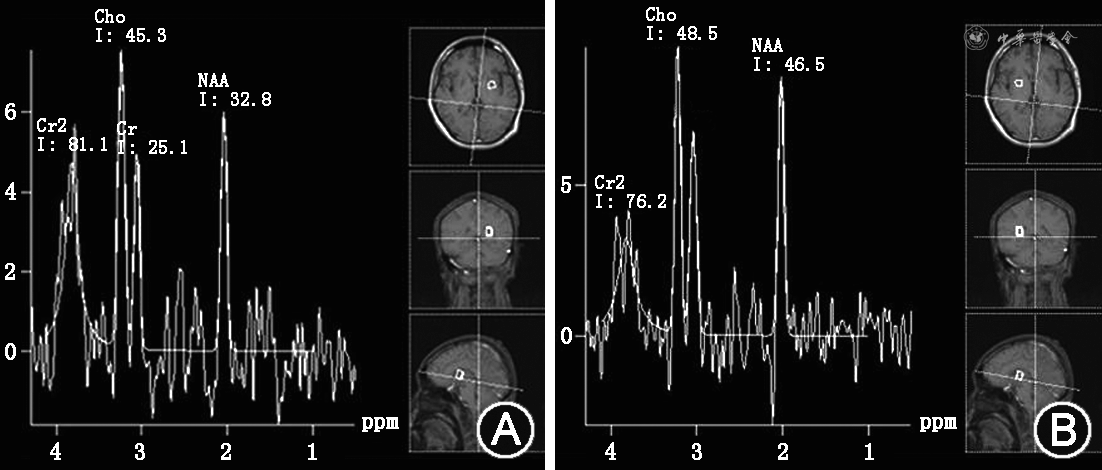

患者男性,29岁,因“发作性肢体抽搐3 d”于2019年12月13日于南京医科大学附属无锡人民医院神经内科住院。患者于3 d前出现左上肢抽搐,持续数十秒,伴左手麻木无力;2 d前出现右上肢抽搐2次,每次持续1 min左右,在当地医院就诊过程中出现发作性意识丧失,双眼向右凝视,牙关紧闭,四肢抽搐2次,每次持续1 min左右缓解。头颅CT:双侧基底节区可疑稍低密度影;头颅CTA:大血管未见明显狭窄。发病以来无感染、发热,无外伤、疫苗接种史,体重无明显下降。既往病史:7岁时有症状性癫痫、昏迷病史,当时考虑疑似脑干脑炎。父母体健,为姨兄妹近亲结婚,母亲有1次无明显原因流产史。体格检查:生命体征平稳,头发稀疏,色偏黄,其他内科体格检查未见明显异常。神经系统体格检查:意识清楚,双侧眼球向内、向上、向下活动受限,双眼水平眼震,右侧鼻唇沟浅,四肢肌力Ⅳ级,四肢肌张力、腱反射、深浅感觉正常,双侧指鼻试验不准,双侧跟膝胫试验不准,双侧病理征、脑膜刺激征阴性。辅助检查:(1)实验室检查:天冬氨酸氨基转移酶107 U/L(正常值15~40 U/L),丙氨酸氨基转移酶40 U/L(正常值9~50 U/L),乳酸脱氢酶325 U/L(正常值120~250 U/L),肌酸激酶8 498 U/L(正常值50~310 U/L),肌酸激酶-MB同工酶17.9 U/L(正常值0~12 U/L),风疹病毒抗体-IgG 15.50 IU/ml(正常值0~10 IU/ml),维生素B12 75 pmol/L(正常值133~675 pmol/L),叶酸 4.09 nmol/L(正常值7.0~45.1 nmol/L),同型半胱氨酸 33.40 μmol/L(正常值4.0~15.4 μmol/L),风湿免疫指标、肿瘤指标、甲状腺功能及相关抗体、铜蓝蛋白、血乳酸、血气分析结果均在正常范围。(2)腰椎穿刺:测压正常,脑脊液常规、生化、病原学检查、免疫球蛋白水平均在正常范围。(3)尿液有机酸分析:甲基丙二酸正常。(4)腹部超声、心脏超声、肌电图检查未见明显异常;动态脑电图:尚在正常范围内(基本节律以低幅β波为主)。(5)头颅MRI:脑干、双侧尾状核、豆状核、丘脑、额颞顶叶、右侧枕叶皮质下异常信号,呈T1低信号(图1A~E)、液体衰减反转恢复序列(FLAIR)高信号(图1F~J),部分弥散加权成像(DWI)高信号(图1K~O);增强头颅MRI:增强后双侧额顶皮质部分病灶可见斑片状强化,双侧基底节区病灶可见结节状及环状强化(图1P~S);磁共振波谱:基底节感兴趣区胆碱峰轻度升高,N-乙酰天冬氨酸峰轻度减低,未见脂质峰或乳酸峰(图2)。(6)基因检测:经知情同意后抽取患者及其父母外周静脉血3 ml,应用二代目标区域捕获测序与Sanger测序验证发现SLC19A3基因的NM_025243:C.1066A>C纯合变异(图3A),其父母该位点均为杂合变异(图3B、C),该变异发生在第4号外显子区,使得第356位的天冬酰胺变异为组氨酸。应用PolyPhen-2预测该变异,结果为致病性的,MutationTaster、SIFT、LR、RialSVM等预测该变异为良性的或可耐受的,目前未见该变异在相关文献或数据库中的报道。

Cr:肌酸